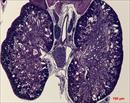

Caption: Mutant 1163-006-NA shows cystic kidneys with cysts in the tubules (details)

Represented Alleles:

b2b1163Clo, Mutant line 1163; Bench to Bassinet Program (B2B/CVDC), mutation 1163 Cecilia Lo

Tmem67b2b1163.1Clo, transmembrane protein 67; Bench to Bassinet Program (B2B/CVDC), subline 1163.1 Cecilia Lo

Copyright: This image is from the Laboratory of Dr. Cecilia Lo, a member of the Cardiovascular Development Consortium (CvDC), Bench to Bassinet (B2B) program of the National Heart Lung and Blood Institute (NHLBI), and is displayed with the permission of the authors. J:175213